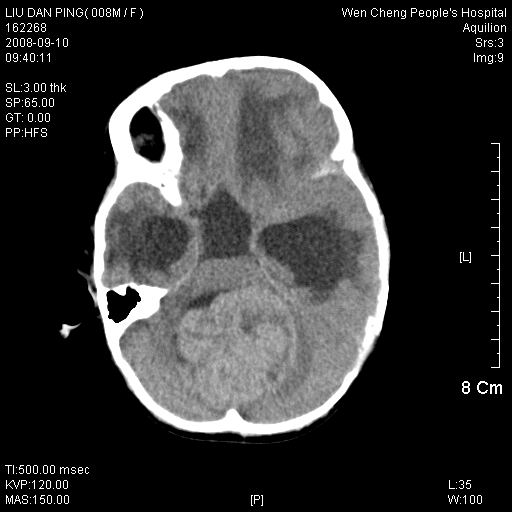

以下是引用卜一在2008-9-10 16:21:00的发言:[br]髓母细胞瘤伴梗阻性脑积水!支持![br]髓母细胞瘤特点:—般直径大于3.5cm,位于后颅凹中线之小脑蚓部。累及上蚓部的肿瘤延伸到小脑幕切迹之上,ct平扫肿瘤多呈均匀一致的高或等密度病灶,增强检查呈均匀一致的强化。病灶中有小坏死时,平扫亦可呈不均匀之混杂密度,注药后有增强。[br]

以下是引用zjzjr在2008-9-10 15:09:00的发言:[br]髓母细胞瘤伴梗阻性脑积水.